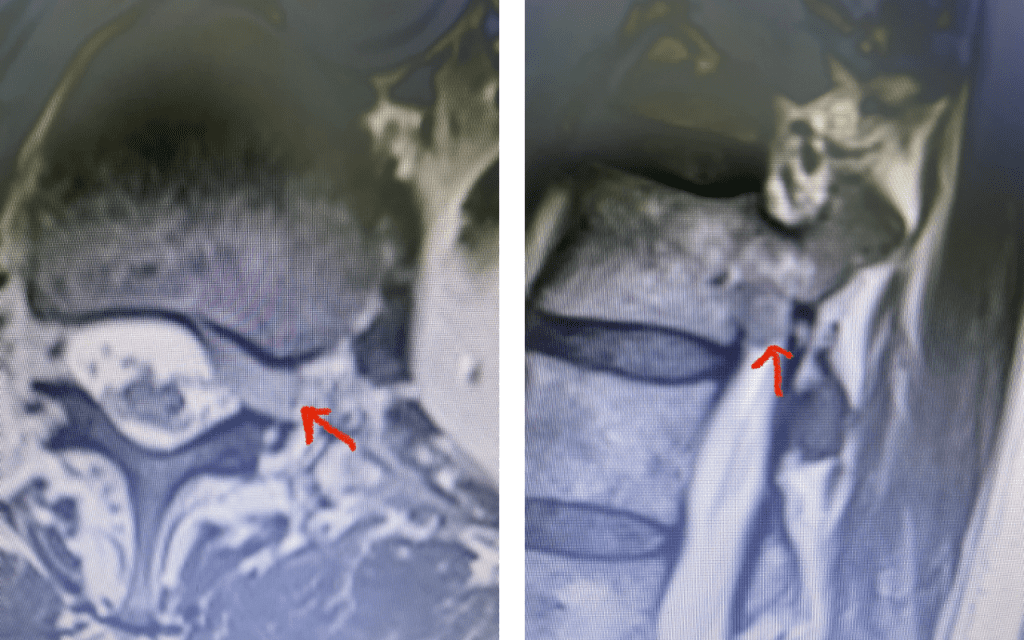

Fig 7: Sagittal T2-weighted lumbar MRI with side by side comparison of the normal open right L3-4 foramen (red arrow) compared to the left L3-4 foramen filled with a large disc fragment (red arrow).